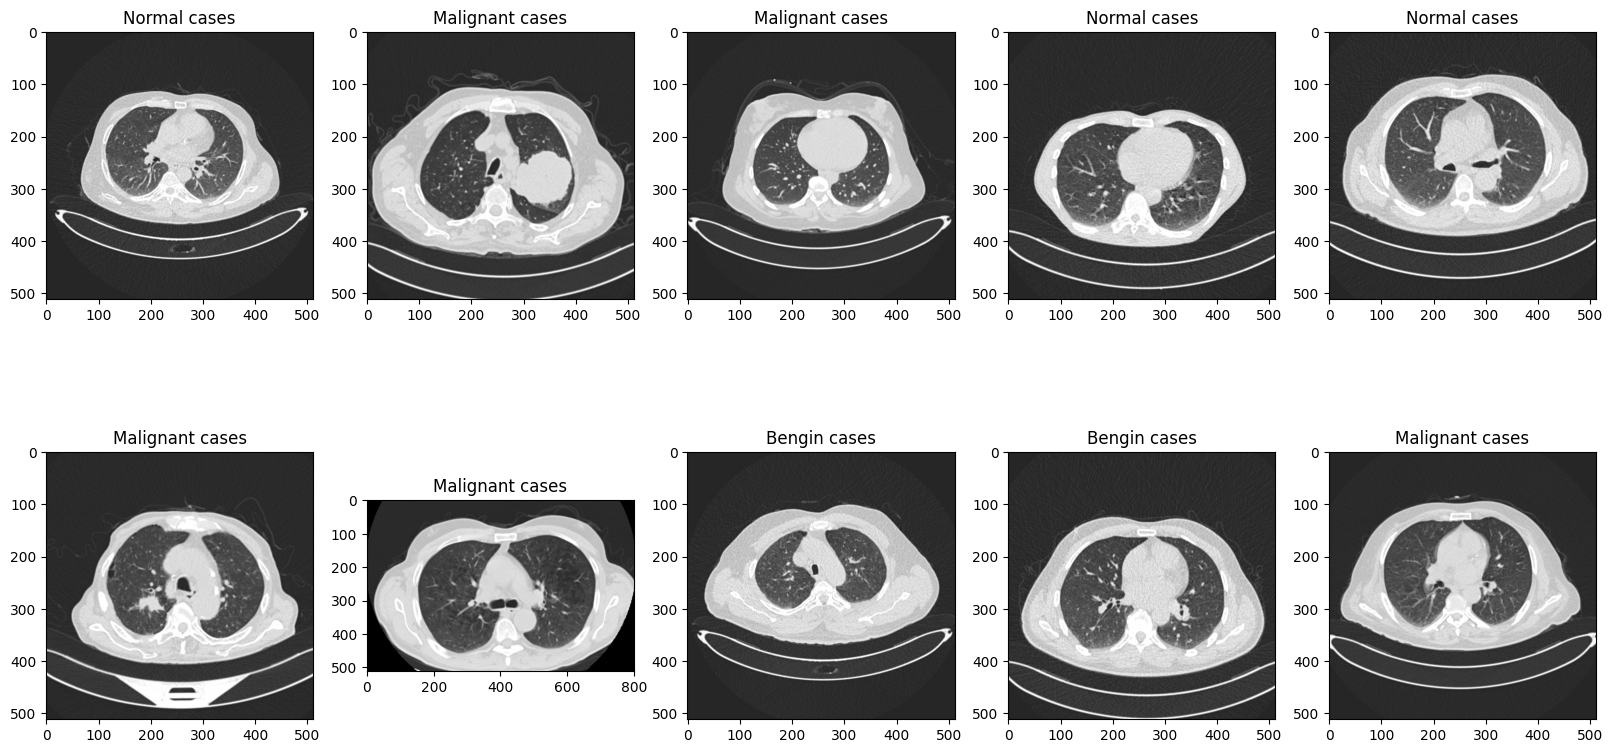

test_file_list = glob.glob(f'{test_root}/*/*')

random.shuffle(test_file_list)

#시각화

plt.figure(figsize=(20, 10))

for i in range(10):

test_img_path = os.path.join(test_root, test_file_list[i])

ori_img = Image.open(test_img_path).convert('RGB')

plt.subplot(2, 5, (i+1))

# /content/The IQ-OTHNCCD lung cancer dataset/lung_cancer/test/Bengin cases/Bengin case (10).jpg

plt.title(test_file_list[i].split('/')[-2])

plt.imshow(ori_img)

test_root에있는 모든 파일들을 다 가지고와서 test_file_list에 넣어줍니다.

그 부분또한 셔플을 넣어주고

파일이 어떻게 들어가있는지 확인해보기 위해서 plt로 시각화를 해보겠습니다.

각img들을 모두 연결해주어서 IMG를 RGB로 연결해주어서 보여주겠습니다.

그다음 -2가지 잘라주는이유는 경로를보면 슬러시를 기준으로 잘라내니까 CLASS이름이 되겠죠?

그 부분을 Title로 삼게됩니다!

사실 비의료진으로서 normal과 begening이 어떤 차이인지는 잘 모르겠더라구요.

vision쪽은 정말 무궁무진하게 사용되는 분야이기때문에 다양한 도메인 지식을 접하고 학습할 수 있는 기회가 많이 생긴다고 하시는데 그 부분도 나에게는 굉장히 큰 cv의 매력으로 다가오게된다.